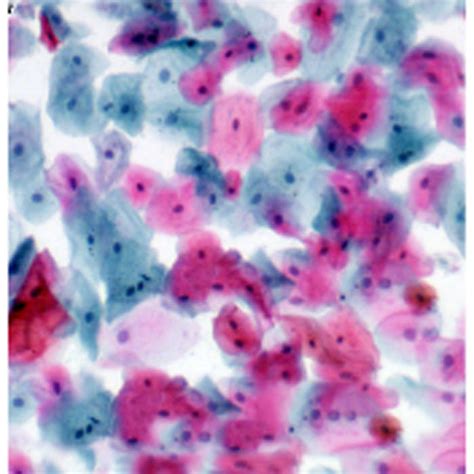

After this procedure, you can observe the slides under a microscope. The elastic fibers will appear black or blue-black, collagen will be red, and other tissue components will be yellow, providing a clear and informative view of the tissue structure. Accurate timing and adherence to the protocol are crucial for achieving optimal staining results.